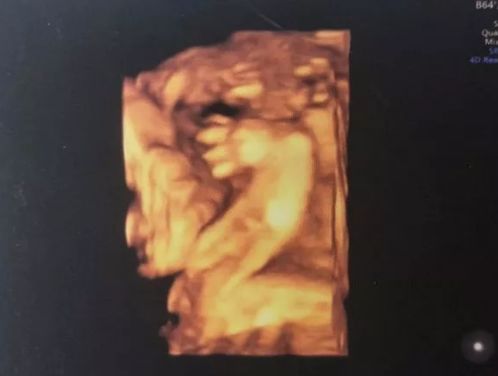

第一次在这家医院做了4维检查,做好之后医生说有27周了,拍出的照片医生说正常。

我保留了我宝宝的4维B超照片,我现在拿来看肉眼明显看到我宝宝的一只手掌张开可清晰看见只有4个手指!!我就不明白了医院医生检查可见的那项上面为什么打印的是:5指可见但不清晰!我很想知道医院医生当时的工作状态为什么会出现这样不负责任.这么不认真?